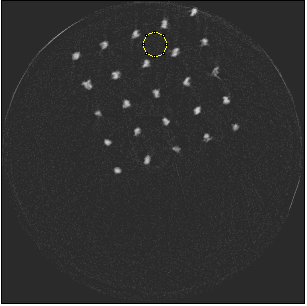

Figure 5 illustrates a single slice spectral reconstruction of the Ti scaffold. Varying levels of streak artefacts can be seen across the spectral reconstructions. The spectral reconstructions for the energy ranges 35 to 80 keV, 55 to 80 keV, and 62 to 80 keV shown in figure 5, exhibit reduced streak artefacts. A region-of-interest (ROI) analysis was performed in the immediate vicinity of the metal region where the streaks are more pronounced. Average attenuation coefficent of air close to zero conveys less regional noise/artefacts. The regional average attenuation coefficient (μROIsubscript𝜇𝑅𝑂𝐼\mu_{ROI}) of the non-metal (air) region in 55 to 80 keV reconstruction (figure 5c) shows reduced artefacts. Even though minor streaks and statistical noise appear in figure 5d due to photon limitation, the artefacts are less pronounced in comparison to the wide energy acquisition in figure 5a.

Refer to caption

(a) 15 to 80 keV

(b) 35 to 80 keV

(c) 55 to 80 keV

(d) 62 to 80 keV

Figure 5: Single slice spectral reconstruction of Ti scaffold sample. μROIsubscript𝜇𝑅𝑂𝐼\mu_{ROI} is 0.246, 0.030, 0.008 and 0.103 for the circular ROI in (a), (b), (c) and (d) respectively.